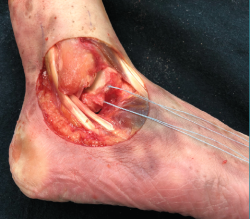

- A continuación, seccionamos el LTFA (Figura 3) con el objeto de reproducir la lesión más frecuente del complejo lateral del tobillo y repetimos la misma secuencia registrando los movimientos angulares detectados en el artrómetro.

Figura 3. Sección de la inserción fibular del ligamento talofibular anterior (reproducimos la lesión más frecuente en la inestabilidad lateral crónica de tobillo).